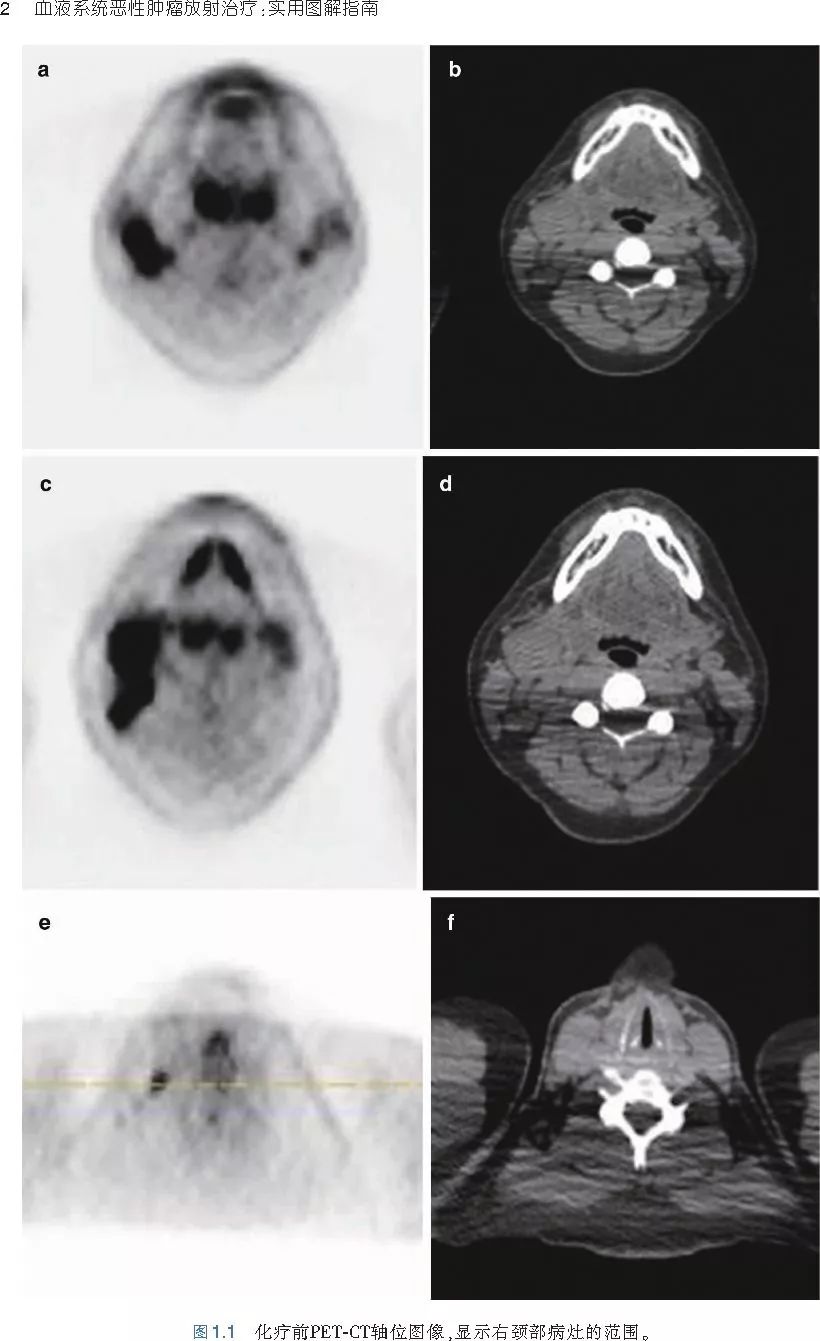

❤ 展开疾病诊断、病理描述及治疗方向的详细阐述,包含医学影像,图文并茂,深入浅出。

本书旨在帮助临床医生对常见血液系统恶性肿瘤疑难病例进行管理,包括霍奇金淋巴瘤、非霍奇金淋巴瘤和白血病患者,并通过多个病例进行阐述。案例讨论遵循标准格式,包括临床描述,其次是与诊断相关的病理描述和分期,然后详细讨论治疗选择。最后,确定治疗方案,并提供所使用的规划放疗技术/方式的图像。对放射肿瘤医生进行临床决策非常有帮助,对于血液病临床医生也有很好的指导作用。

近年来,放射治疗技术得到了迅速发展,调强放疗、图像引导放疗及其他新技术方法等,对恶性肿瘤治疗产生了巨大影响。现代放疗技术使精确定位、靶区勾画及给量成为可能,实现了肿瘤局控率和生活质量的双赢,对血液系统恶性肿瘤的临床治疗也产生了一定的影响。此书内容上不仅反映了血液系统恶性肿瘤综合治疗的进步,更是对其中放射治疗的新变化进行了系统、详细的阐述,这对当前血液系统恶性肿瘤放射治疗临床实践具有非常好的指导作用和参考价值。